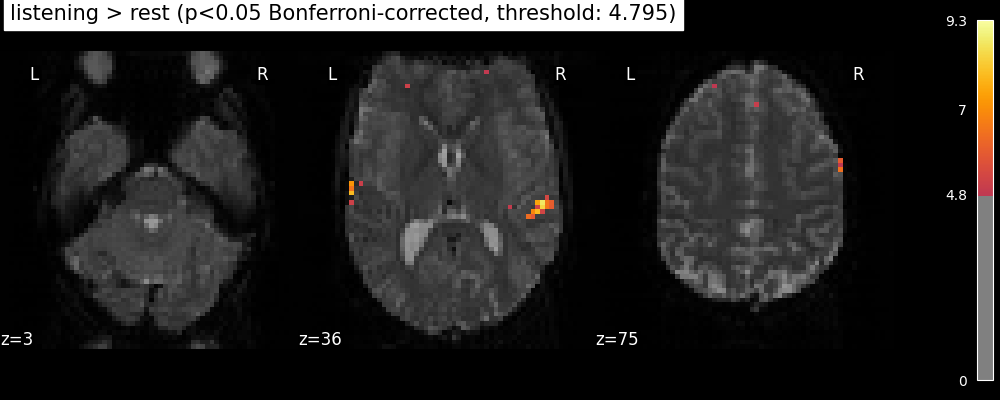

The problem is that with this you expect 0.001 * n_voxels to show up while they’re not active — tens to hundreds of voxels. A more conservative solution is to control the family wise error rate, i.e. the probability of making only one false detection, say at 5%. For that we use the so-called Bonferroni correction.

clean_map, threshold = threshold_stats_img(

z_map, alpha=0.05, height_control="bonferroni", two_sided=False

)

plot_stat_map(

clean_map,

threshold=threshold,

title=(

"listening > rest (p<0.05 Bonferroni-corrected, "

f"threshold: {threshold:.3f})"

),

figure=plt.figure(figsize=(10, 4)),

**plotting_config,

show()

This is quite conservative indeed! A popular alternative is to control the expected proportion of false discoveries among detections. This is called the False discovery rate.